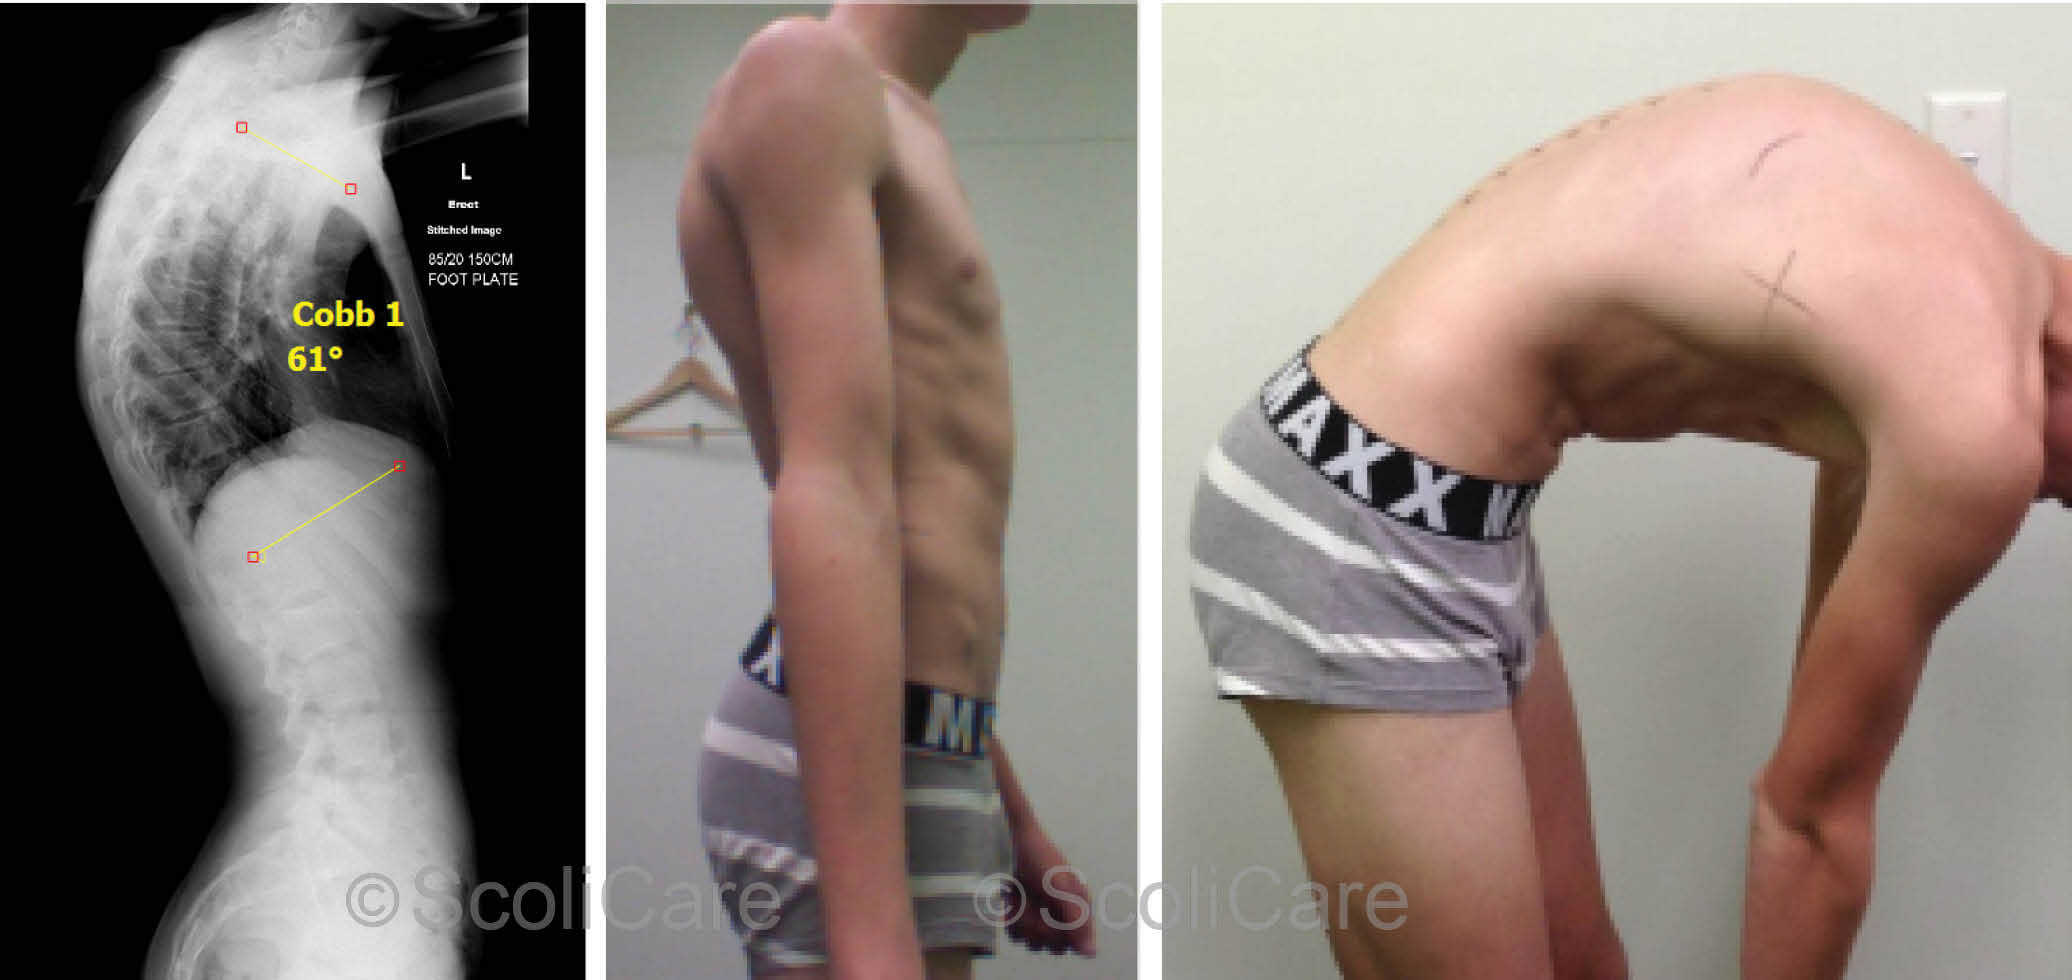

Измерение кифоза грудного отдела: Рентгеновские снимки